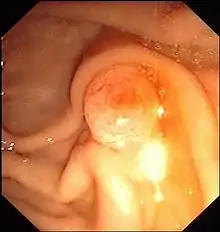

Ендоскоп вводиться через рот в дванадцятипалу кишку, де оглядається і зондується фатеровий сосочок (Papilla vateri), гирло спільної протоки жовчних і підшлункових вивідних шляхів. Контрастна речовина вводиться в жовчні протоки ретроградно, тобто всупереч нормальному напрямку потоку жовчі. Під рентген контролем оцінюють звуження проток, наприклад, внаслідок жовчних каменів (холедохолітіаз), або пухлин .

Перевагою ЕРХП є можливість також одночасно проводити терапію на додаток до діагностики, наприклад, за допомогою інструменту для видалення або роздрібнення каменю, який просувається по робочому каналу ендоскопа. Це видаляє жовчні камені, які вийшли з жовчного міхура в жовчні протоки і вклинилися на вузькому кінці перед фатеровим сосочком. Якщо камінь занадто великий, щоб пройти через розріз або розширений сосочок, заздалегідь виконують механічну, або лазерну літотрипсію.

Якщо інструменти неможливо просунути в жовчний канал, отвір сосочка розрізається спеціальним катетером з рухомим електрично зарядженим дротом. Цей процес називається ендоскопічною папілотомією (ЕПТ). Іноді сосочковий отвір розширюється за допомогою повітряного балону.